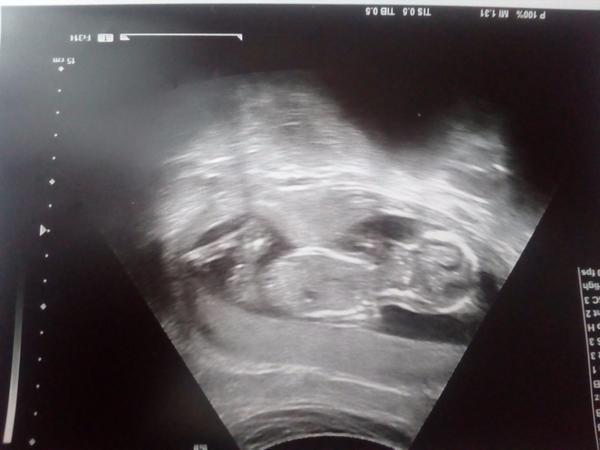

Jinak holky já jsem dnes po screeningu,ačkoli mimčo je menší(11+5)ale krásně roste a má se čile k světu. Ani nevíte jak jsem se v čekárně bála,jak u maturity. Naštěstí to ze mě spadlo

@mari90 nadherna fotka.